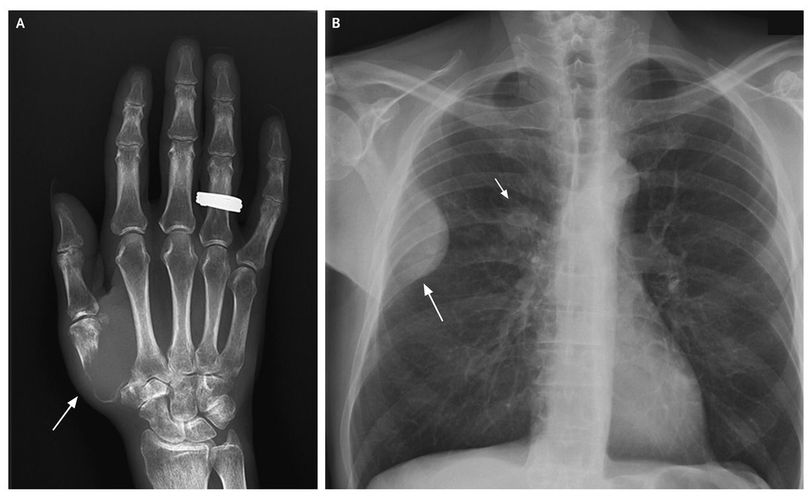

A 59-year-old man presented with a 6-week history of pain in the thumb. He also reported having a cough, weight loss, and a history of heavy smoking. Physical examination revealed swelling, redness, and tenderness over the first right metacarpal and a mass (10 cm in diameter) fixed to the thorax. Laboratory tests revealed a C-reactive protein level of 123 mg per liter and a leukocyte count of 34×109 per liter. A radiograph of the hand showed osteolysis of the first metacarpal (Panel A, arrow), and a chest radiograph showed a solid mass of the thoracic wall expanding into the subpleural space (Panel B, long arrow) and a tumor in the hilus of the right lung (Panel B, short arrow). A specimen of the metacarpal lesion obtained through needle aspiration was negative for bacteria. The final diagnosis was lung adenocarcinoma with osseous lesions of the hand and ribs. The patient received palliative care.